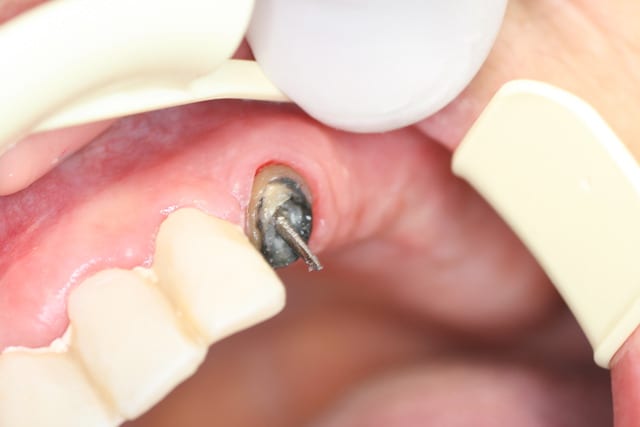

Je n'arrive pas a enlever ce putain de tenon a la base il s agissait

d'un attachement axial (boule ) que je voulais enlever pour faire un inlay core en suite 6 couronnes liées avec 2 attachements extra coronaires.

Donc soit je continue et je risque de fracturer la racine ou de couper la partie externe au ras du canal , soit j 'essaie de constituer une reconstitution à base de compo mais avez vous du recul sur ce type de "bricolage" ?

PS: un détail la patiente a mal lors que je force trop que cela soit avec une fraise ou des us ...